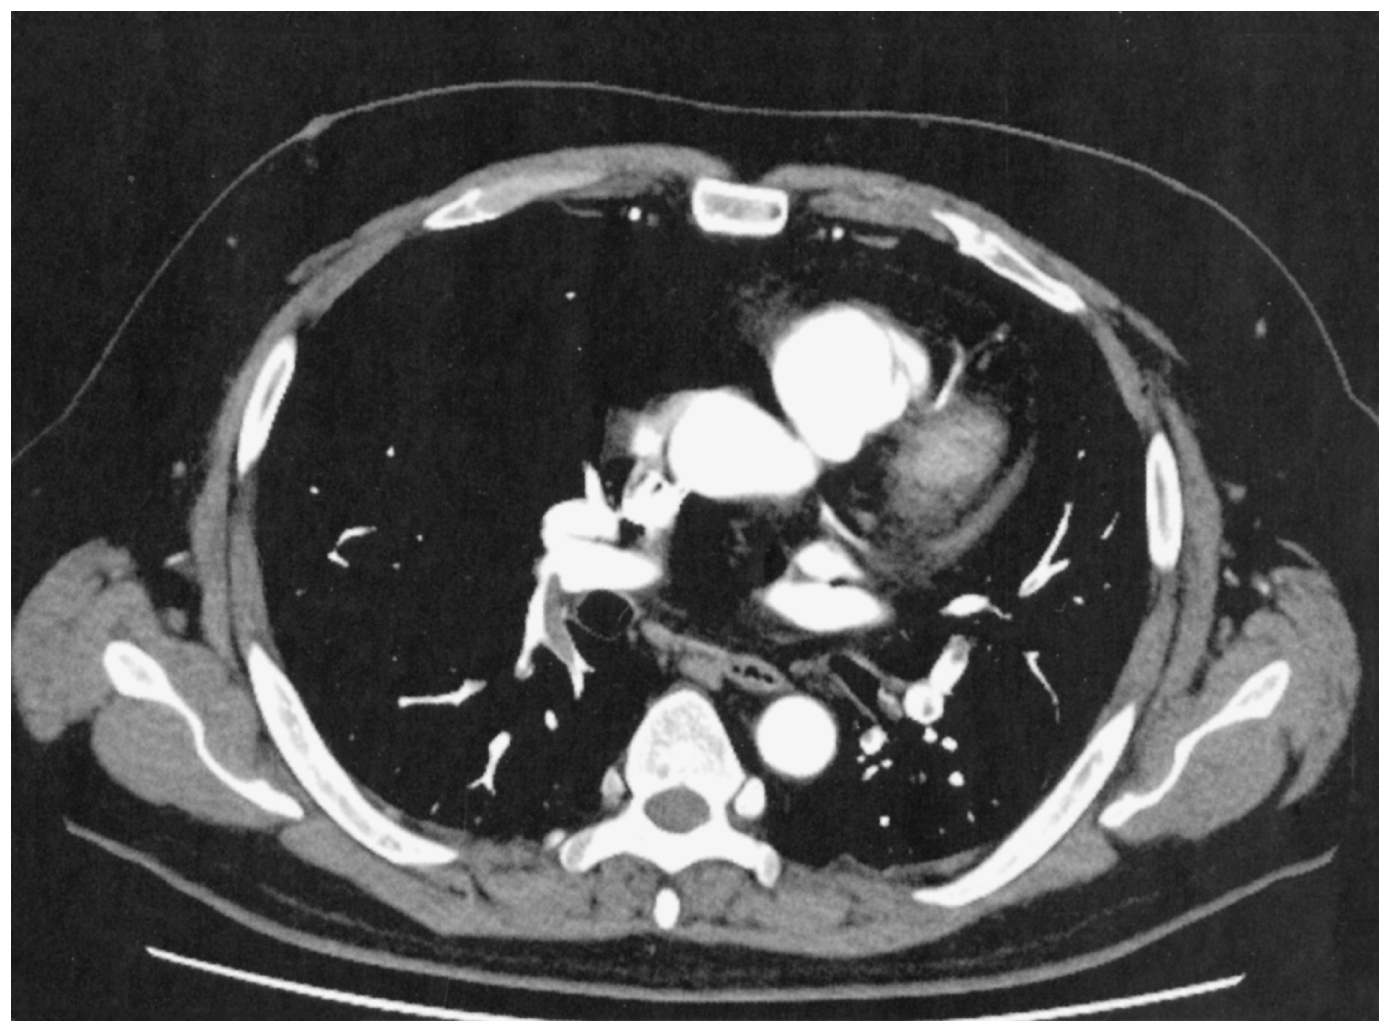

58歳の男性。労作時の呼吸困難を主訴に来院した。今朝,起床後から労作時呼吸困難が出現した。通常通りに出勤したが呼吸困難が持続しており,処方されていた吸入薬を使用後も改善がみられなかったため受診した。35歳時から①喘息に対して吸入療法中。57歳時から②臨床病期Ⅳ期の非小細胞肺癌に対して治療中③2週間前にインフルエンザワクチン接種を受けた④築35年の木造住宅に住んでいる。⑤自宅で鳥を飼育している。意識は清明。身長172cm,体重67kg。体温36.5℃。脈拍92/分,整。血圧138/90mmHg。呼吸数20/分。SpO2 92%(room air)。頸静脈の怒張と口唇のチアノーゼとを認めない。心雑音を聴取しないが胸骨左縁第2肋間でⅡ音の亢進を認める。呼吸音に異常を認めない。下腿に浮腫を認めない。血液所見:赤血球452万,Hb 13.8g/dL,Ht 41%,白血球5,400,血小板21万,PT-INR 1.0(基準0.9~1.1),Dダイマー4.4μg/mL(基準1.0以下)。血液生化学所見:総ビリルビン1.0mg/dL,AST 21U/L,ALT 9U/L,LD 306U/L(基準124~222),CK 60 U/L(基準59~248),尿素窒素11mg/dL,クレアチニン0.6mg/dL,血糖114mg/dL。胸部造影CTを下に示す。

無料会員登録していただくと、実際の解説をすべて見ることができます。急性の呼吸困難を主訴とする疾患としては,喉頭浮腫,気道異物,自然気胸,気管支喘息,慢性閉塞性肺疾患の急性増悪などの呼吸器疾患,心不全(急性,慢性の急性増悪),肺血栓塞栓症などの循環器疾患が代表的である。この症例では呼吸器感染症と心不全が疑われるが,胸部エックス線写真は肺炎像というよりも両心不全を示唆する所見を示している。診断:心不全(両心不全)(Nohria分類wet and warm) 選択肢考察 ×a 強い呼吸困難,胸痛などにより安静が保てない場合には,血管拡張による前負荷軽減と,交感神経抑制による心筋酸素消費量の減少を目的としてモルヒネを使用する。この症例ではモルヒネが必要となるほどの興奮状態ではない。